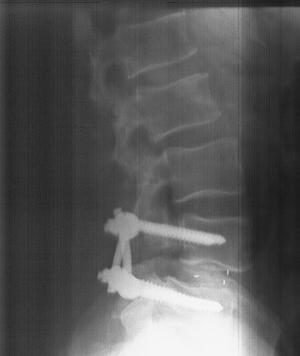

During the 6 1/2-hour operation, the doctor made a 12-in. incision in my back, cutting away all the "unnecessary" bone around the vertebrae and also removing the soft disc between the two vertebrae. Then he packed the open area with my own ground-up bone which had been mixed with a special protein that makes it grow. He then inserted four large titanium "lag bolts" and two rods to secure the two vertebrae while the bone "grows" and hardens. Once the fusion hardens û it takes about 6 months û the metal hardware will serve no purpose. However, they generally don't take them out because they're buried under layers of skin and muscle. I can't even feel them.